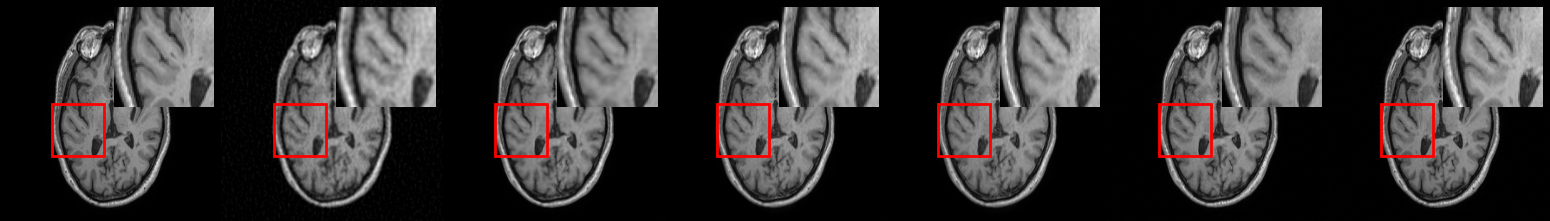

4.2 MRI Reconstruction

Quantitative results for MRI reconstruction are summarized in Table 1. On average, BCDM achieves (pSNR, SSIM, FID) improvements of (4.9dB, 2.1%, 40) over post-conditioned DMs (i.e., DPS, DMPS) and (5.7dB, 1.7%, 23.5) over the conditional DM baseline (i.e., DI). Representative reconstructions in Fig. 2 highlight that BCDM yields superior image quality against competing methods with minimal artifacts and acute structural details. While DI is a conditional DM, it cannot alleviate the global aliasing artifacts in accelerated MRI.

Quantitative results for image deblurring are summarized in Table 1. On average, BCDM achieves (pSNR, SSIM, FID) improvements of (2.5dB, 5.1%, 19.6) over post-conditioned DMs, and (0.3dB, -0.4%, 3.8) over DI (albeit DI yields slightly higher SSIM). Note that image blur is a local artifact that DI can more effectively cope with. However, unlike BCDM, DI still fails to provide theoretical guarantees for learning the true conditional score-function. Fig. 2 displays representative images from competing methods. While averaging across independent samples tends to improve image quality for all methods, BCDM shows notably lower artifacts than competing methods in single image instances.

Quantitative results for image super-resolution (SR) are summarized in Table 1. In this task, the unrolled method performs more comparably with diffusion methods in terms of pSNR and SSIM, and DI yields the highest performance while BCDM performs competitively with generally second-best metrics among DMs. It is important to note that the common quantitative metrics reported here provide global performance measures that are insufficiently sensitive to detailed image features, thus visual evaluations serve a critical role in comparative assessments, especially for the SR task where high-frequency features are recovered in the absence of high-frequency data. In terms of visual quality, we find that BCDM outperforms competing methods in spatial acuity, particularly near heterogeneous regions containing object boundaries, as exemplified in Fig. 2.

Finally, to assess the effects of domain shifts in the forward operator on reconstruction performance, we conducted an image inpainting experiment. The domain shift was obtained by using larger pixel-removal masks during training than those prescribed during testing. Note that knowledge of the forward operator only influences conditional DMs, while unconditional DMs are not affected (i.e., DPS, DMPS). Quantitative metrics are summarized in Table 2. The unrolled method is a deterministic approach so it faces difficulty in filling in the masked image region. On average, BCDM achieves (pSNR, SSIM, FID) improvements of (2.9dB, 6.2%, 15.9) over post-conditioned DMs, and (9.7dB, 4.9%, 269.4) over DI. These results suggest that BCDM is more resilient against domain shifts in the forward operator than other DMs. In terms of visual quality, BCDM substantially outperforms competing methods in terms of accuracy of structural details, as seen in Fig. 2.